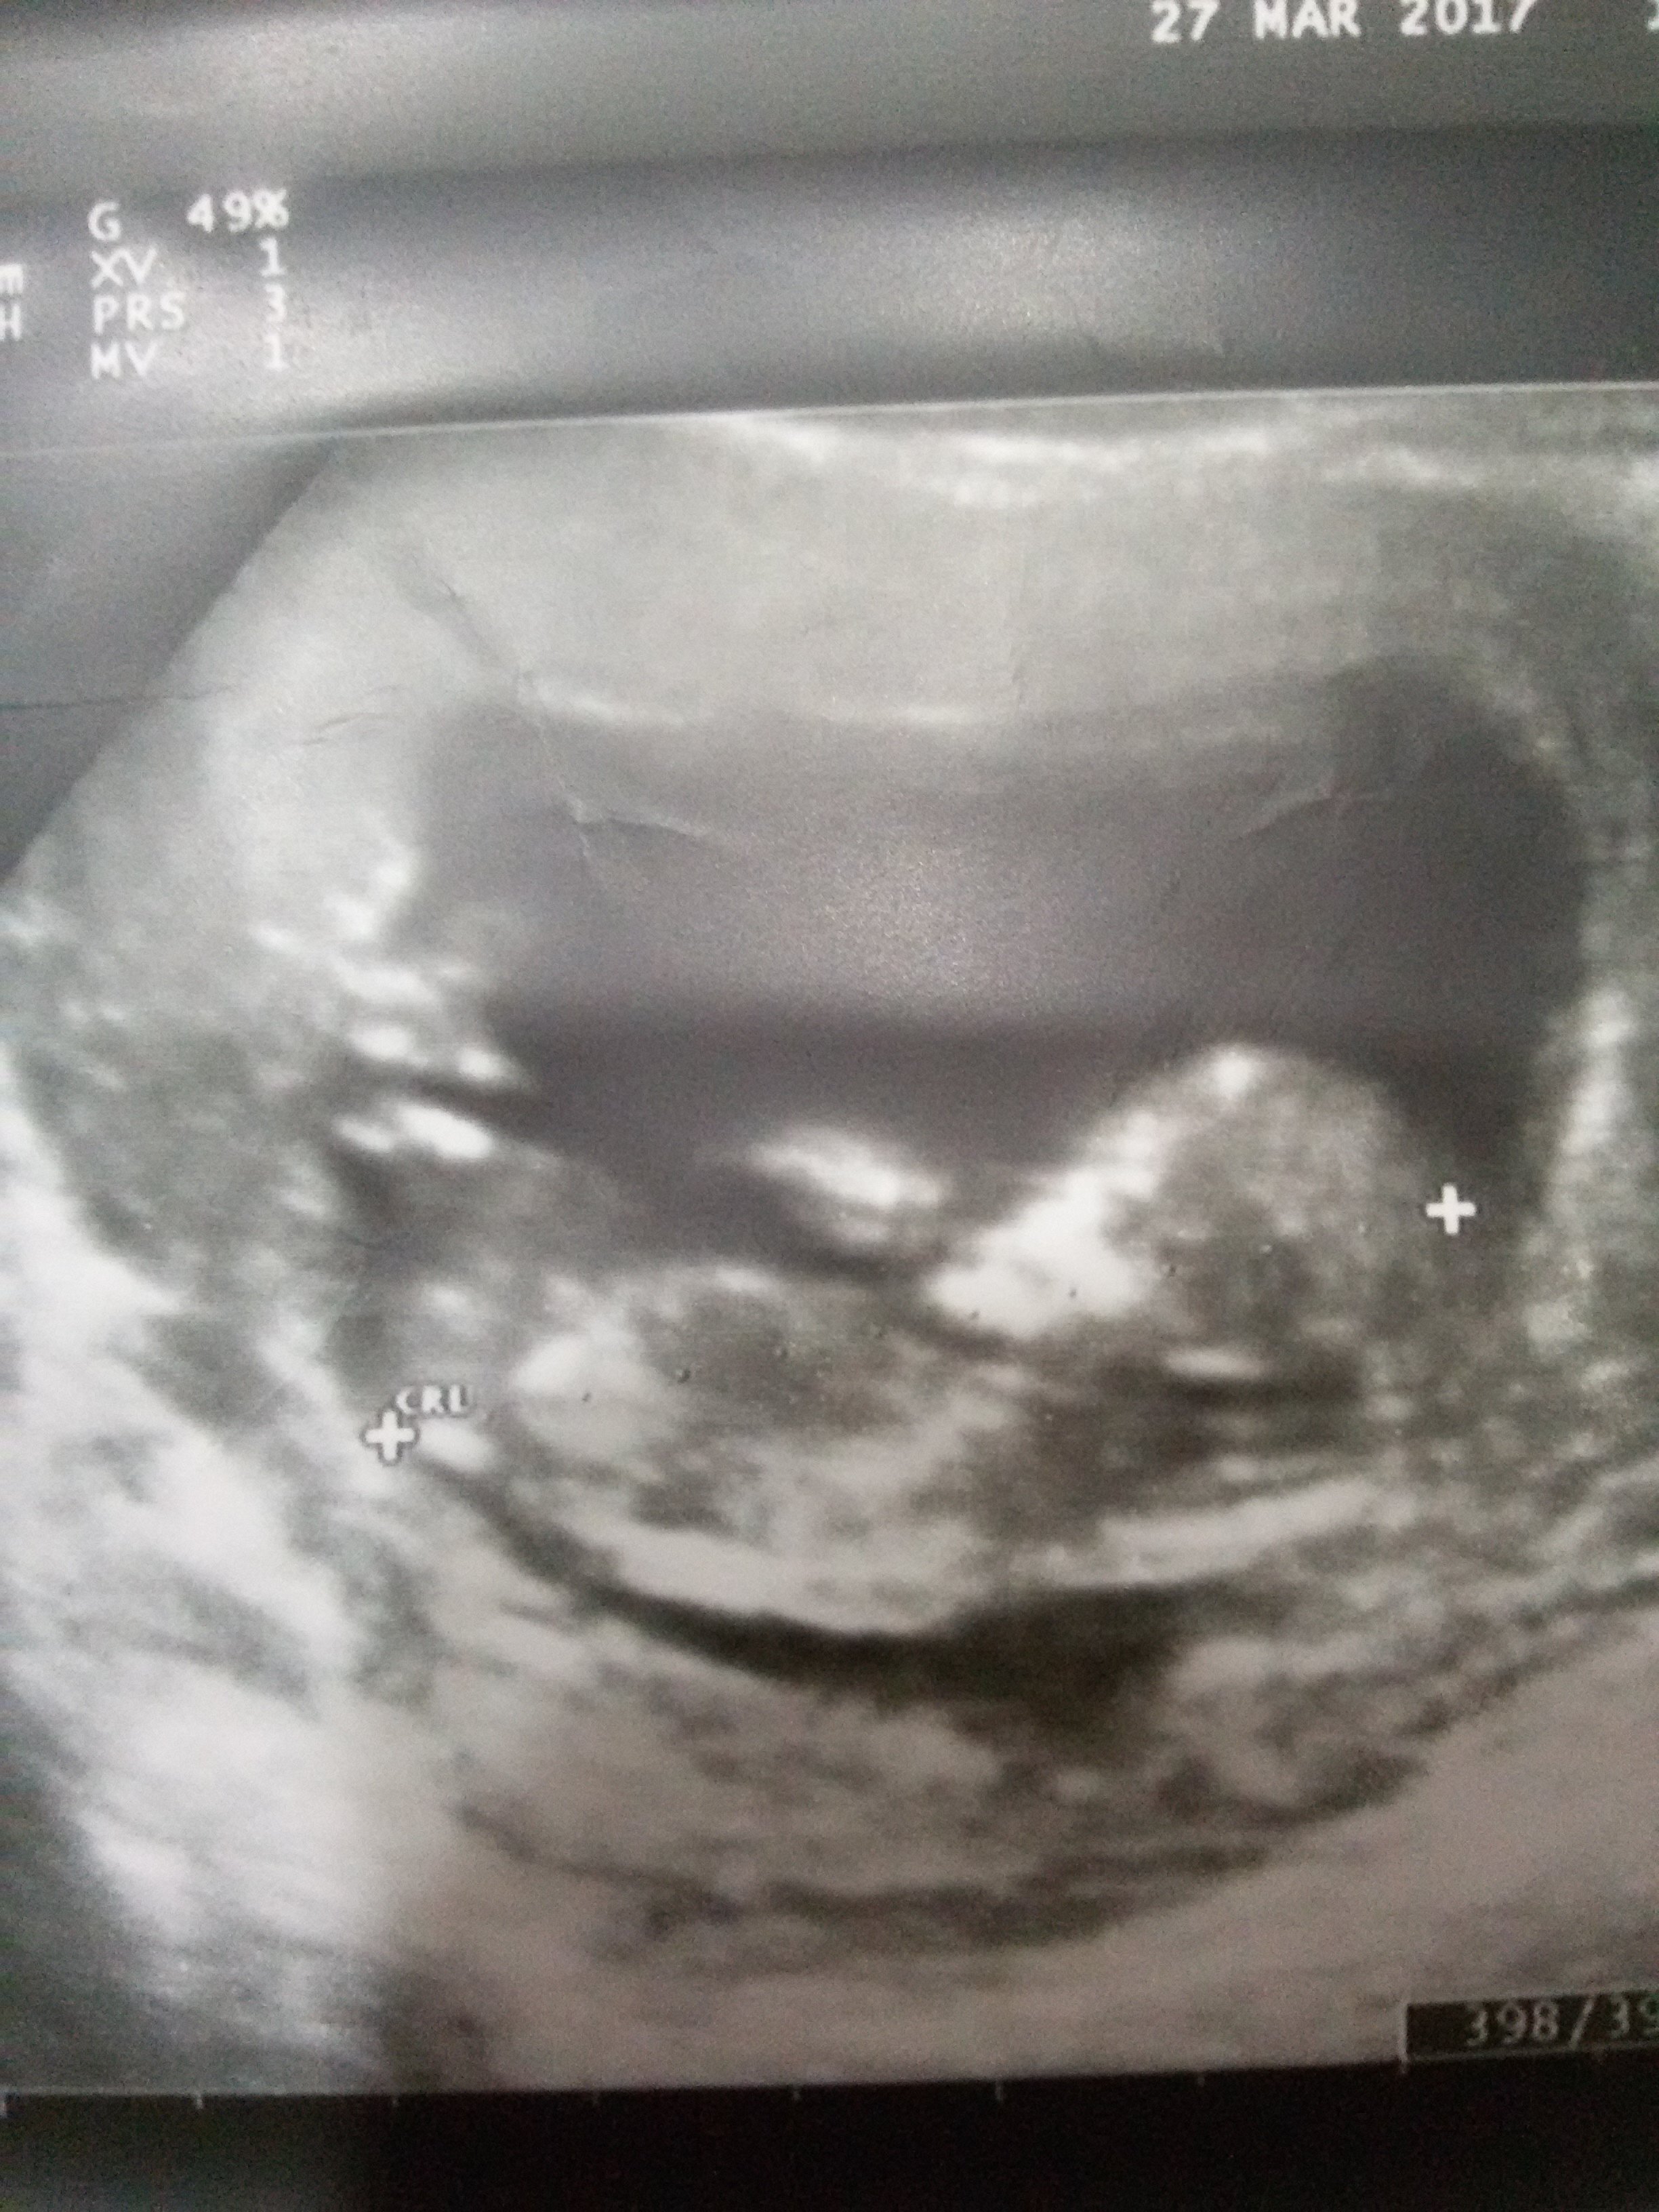

Jaki kolor i jaki zapach? Mamaginekolog to fajnie tłumaczyDziewczyny, czy wy macie takie uplawy coś w stylu takiego gluta? Nie wiem czy się martwić, byłam w piątek na wizycie i zapomniałam o tym powiedzieć co prawda jeśli chodzi o dziecko to na usg wszystko było dobrze.